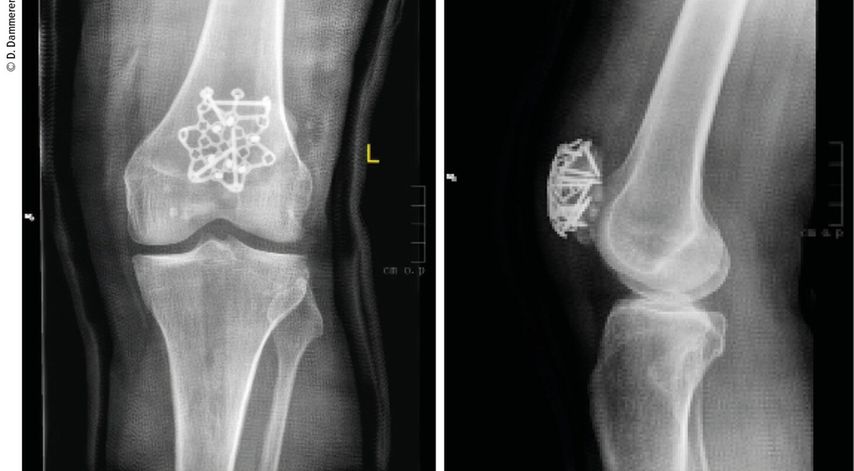

Abb. 2: Die operative Versorgung erfolgte mittels Sternplatte und zeigt ap und seitlich eine gute Reposition aller Frakturfragmente